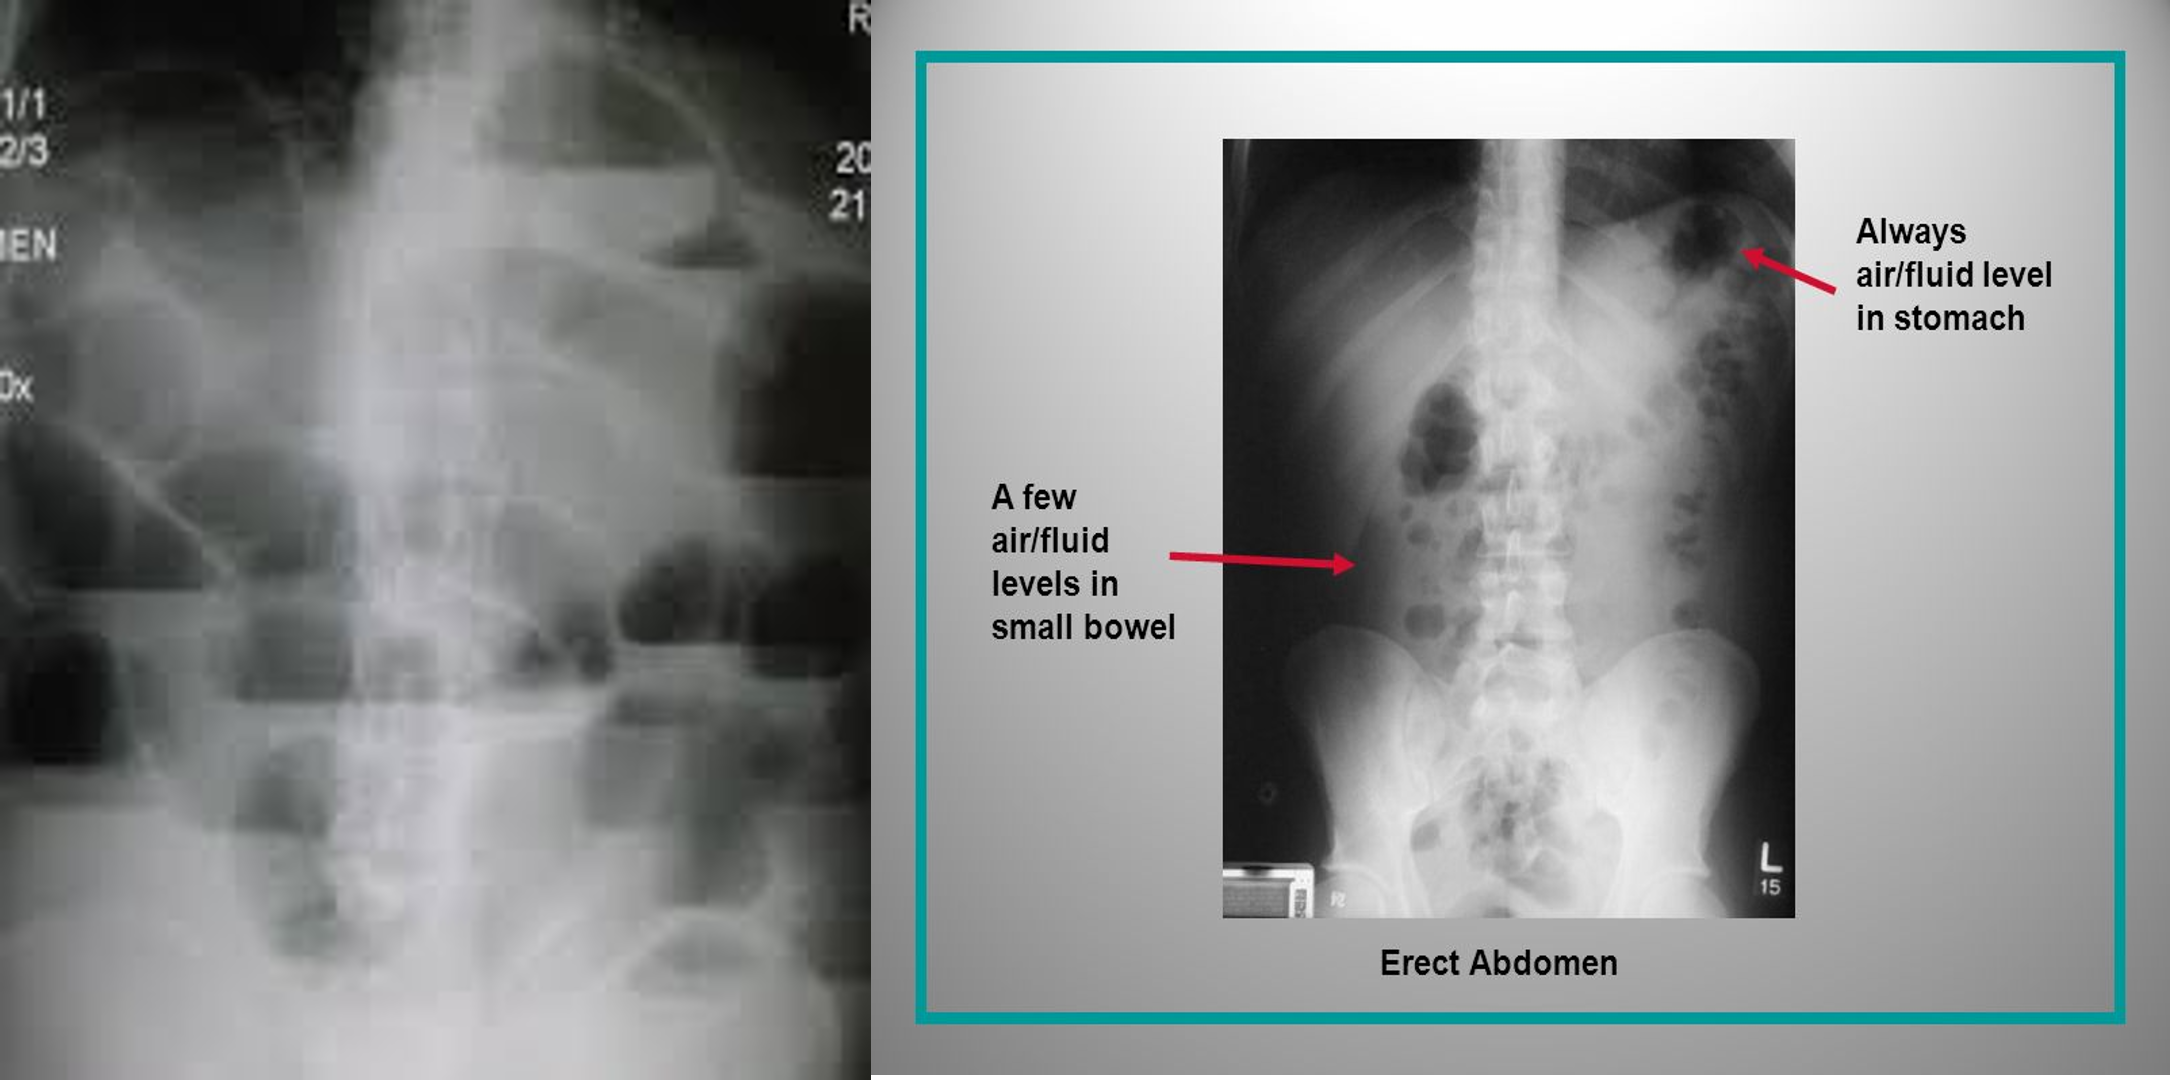

Air-fluid level:

- Visible on upright or decubitus views

- Common criteria for diagnosing SBO 3 air-fluid levels & Air-fluid level diameter > 2.5 cm

Mechanical small bowel obstruction-X-ray abdomen (erect)

Multiple air-fluid levels are visible in the mid-abdomen. The opaque appearance of the pelvis is due to fluid-filled loops of small bowel. There is a paucity of gas in the colon, and an air-fluid level is present in the dilated stomach.